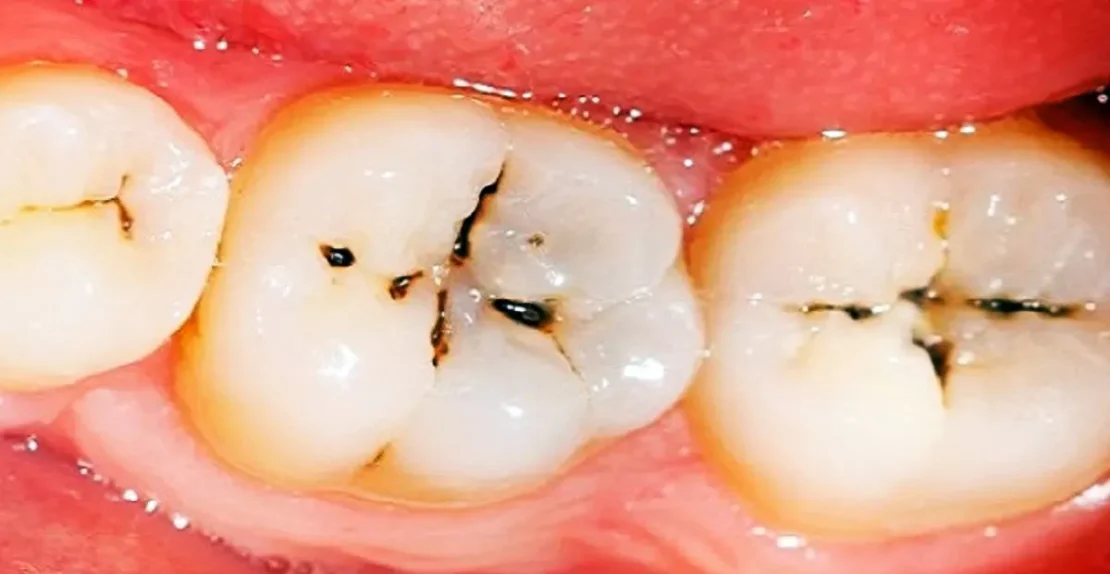

23 مهر مقالات, مقالات ترمیم دندان توضیح اینله و انله به زبان ساده + شرح مراحل 29 آذر 1404 توسط آرتمان درمان 2 دیدگاه در دندانپزشکی چندین نوع روش برای ترمیم دندانهای آسیب دیده و یا دچار پوسیدگی وجود دارد. ما در آرتمان درمان بسته به اینکه مقدار آسیب دید... ادامه مطلب